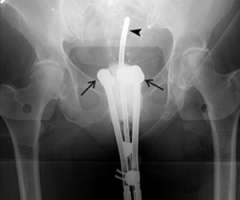

In the images below for example on the right is an anterior-posterior view of a vaginal applicator inserted in the vagina. You can see the cylinder pushing up against the top of the vaginal apex. You can't see the outline of the entire bladder and rectum but one way to approximate them is to place foley catheters in the bladder (yellow outline) and the rectum (brown outline) so they can be visualized.

Our approach at UCLA is to do 3D based instead of 2D based planning for these cases as well. Once again one can immediately appreciate how much additional detail in the anatomy and distribution of the radiation dose can be appreciated on the CT scan versus the X-ray.